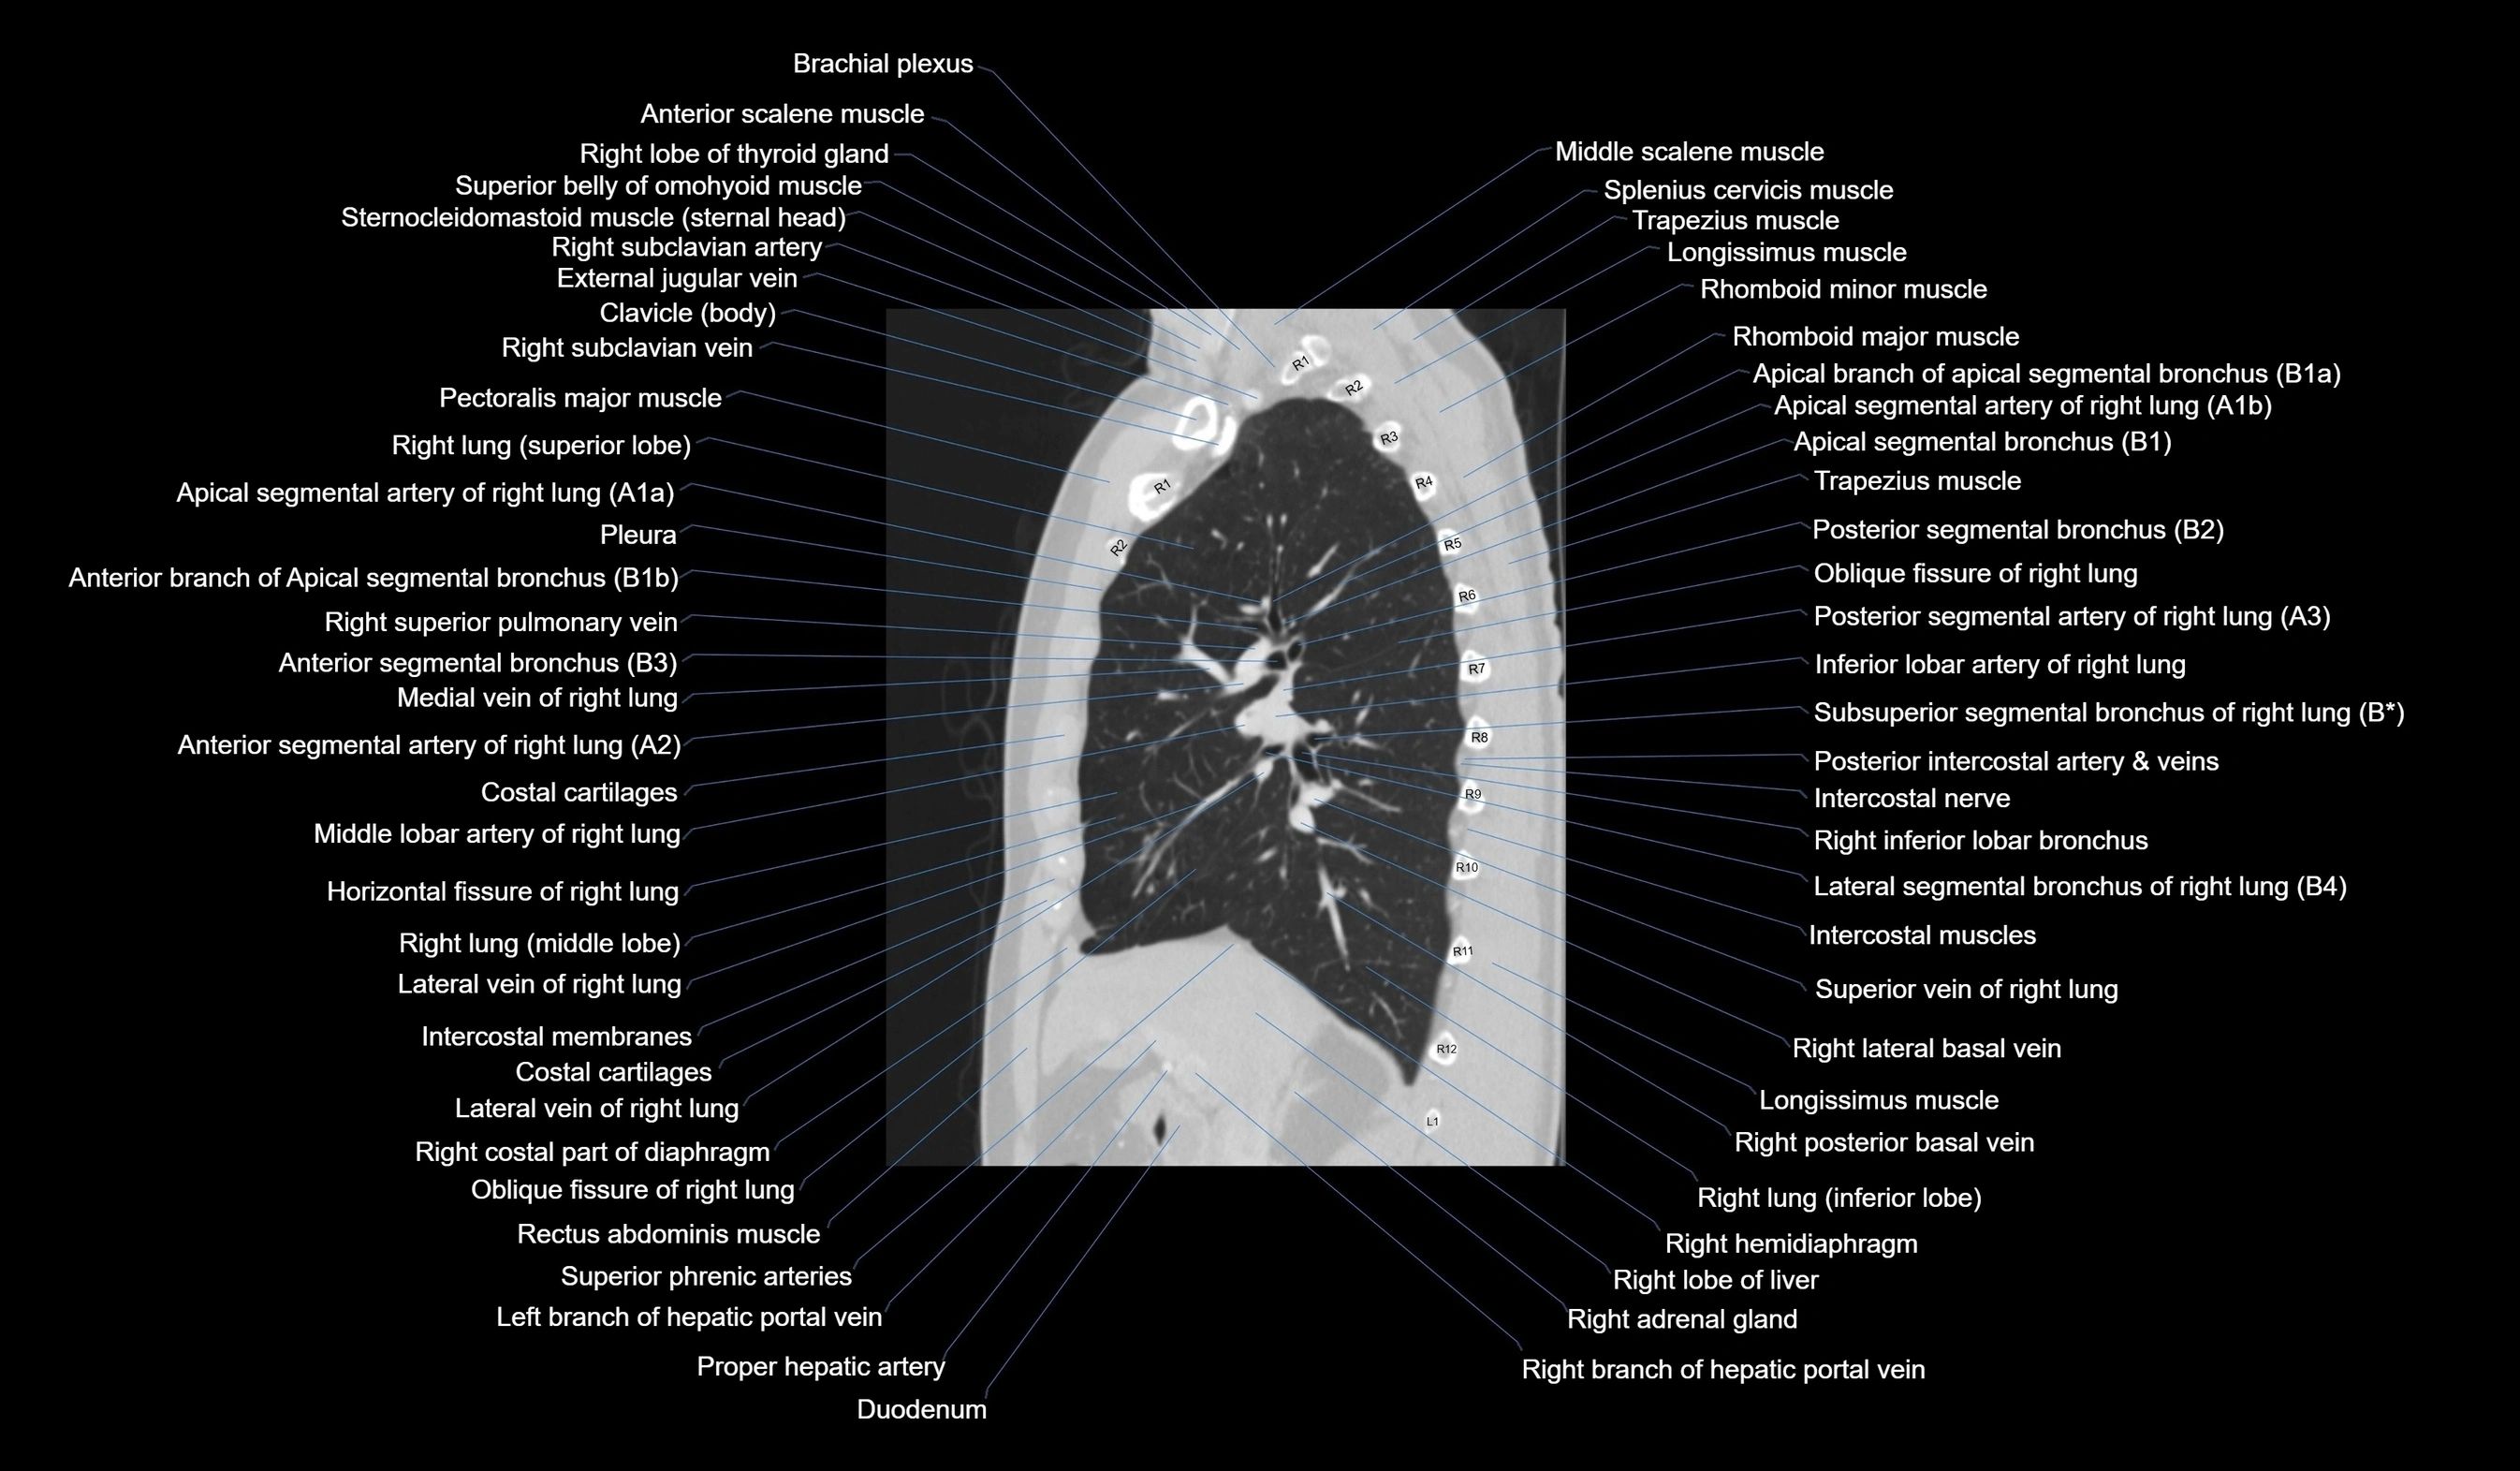

MRI images

CT images